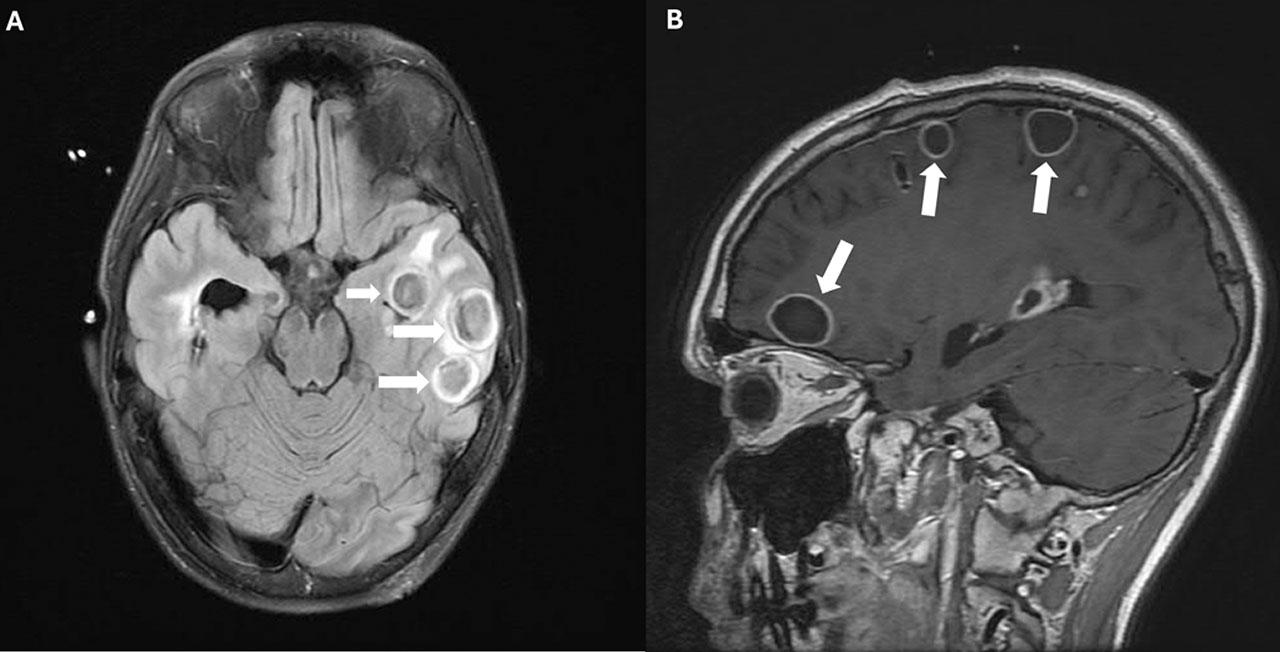

Fig. 2.

A and B Axial MRI images demonstrating resolving brain abscesses. White arrows highlight the reduced size of abscesses